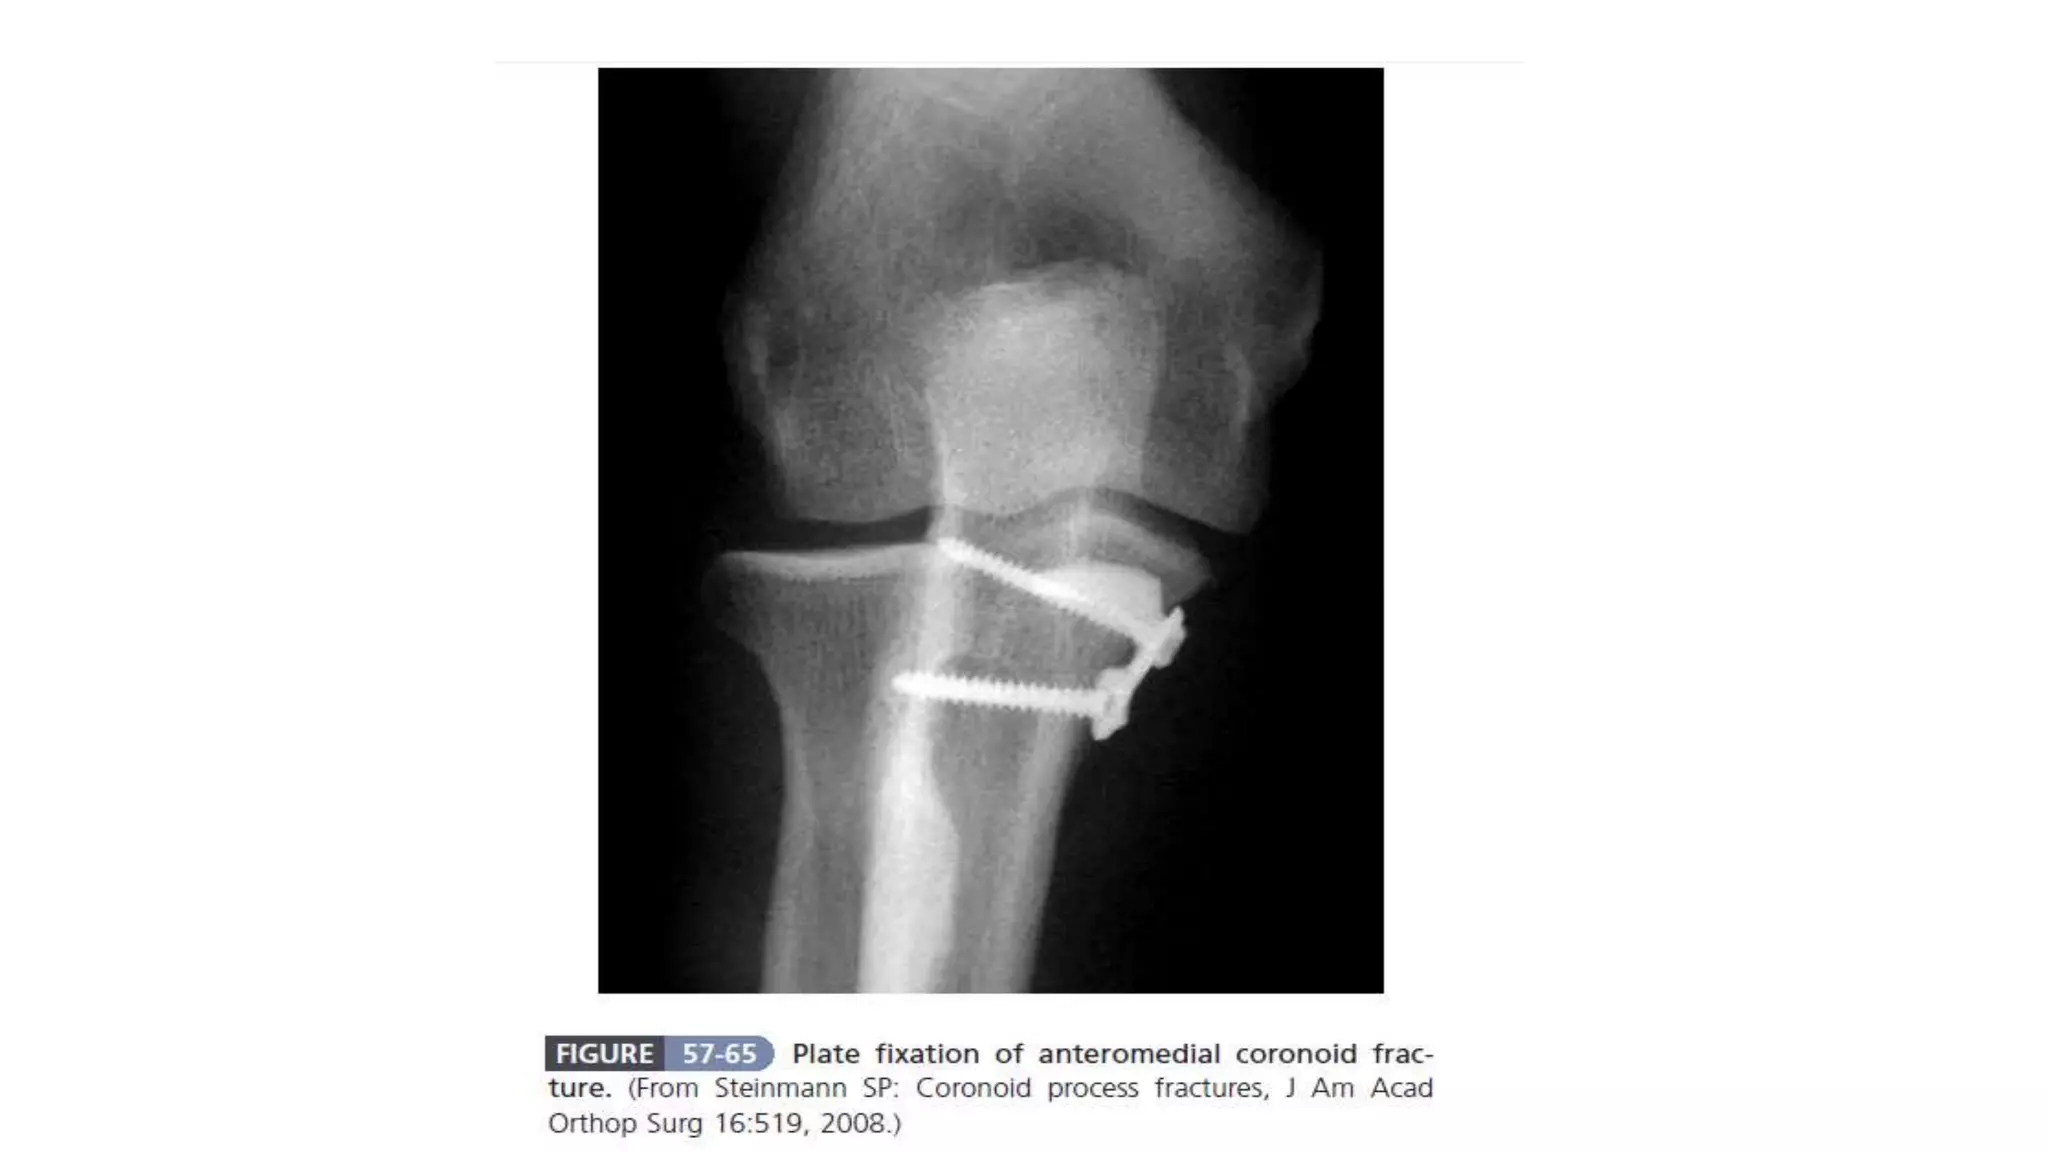

Coronoid fractures occur in 10% to 15% of elbow dislocations and are classified into three types based on the extent of the fracture. Diagnosis may require CT imaging for accurate assessment, and treatment options include sutures for small fragments and lag screws for larger ones. Careful evaluation is essential to rule out associated injuries, and repair of the lateral collateral ligament may be recommended in some cases.